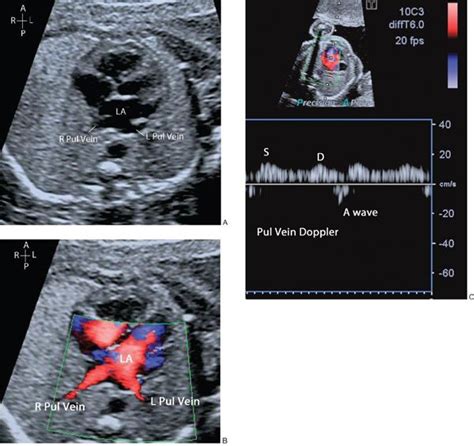

There are other views too, guys! The sonographer might also use views to assess the inferior vena cava (IVC) and the superior vena cava (SVC), which are major veins that carry blood back to the heart. They might also look at the aortic arch and the ductus arteriosus. The ductus arteriosus is a blood vessel that connects the pulmonary artery to the aorta in a fetus, and it’s essential for blood circulation before birth. These views help to provide a complete picture of the baby’s circulatory system. The specifics will vary depending on the baby’s position and any concerns the doctor may have. The key is that the sonographer adapts the examination to get the clearest, most comprehensive picture possible.